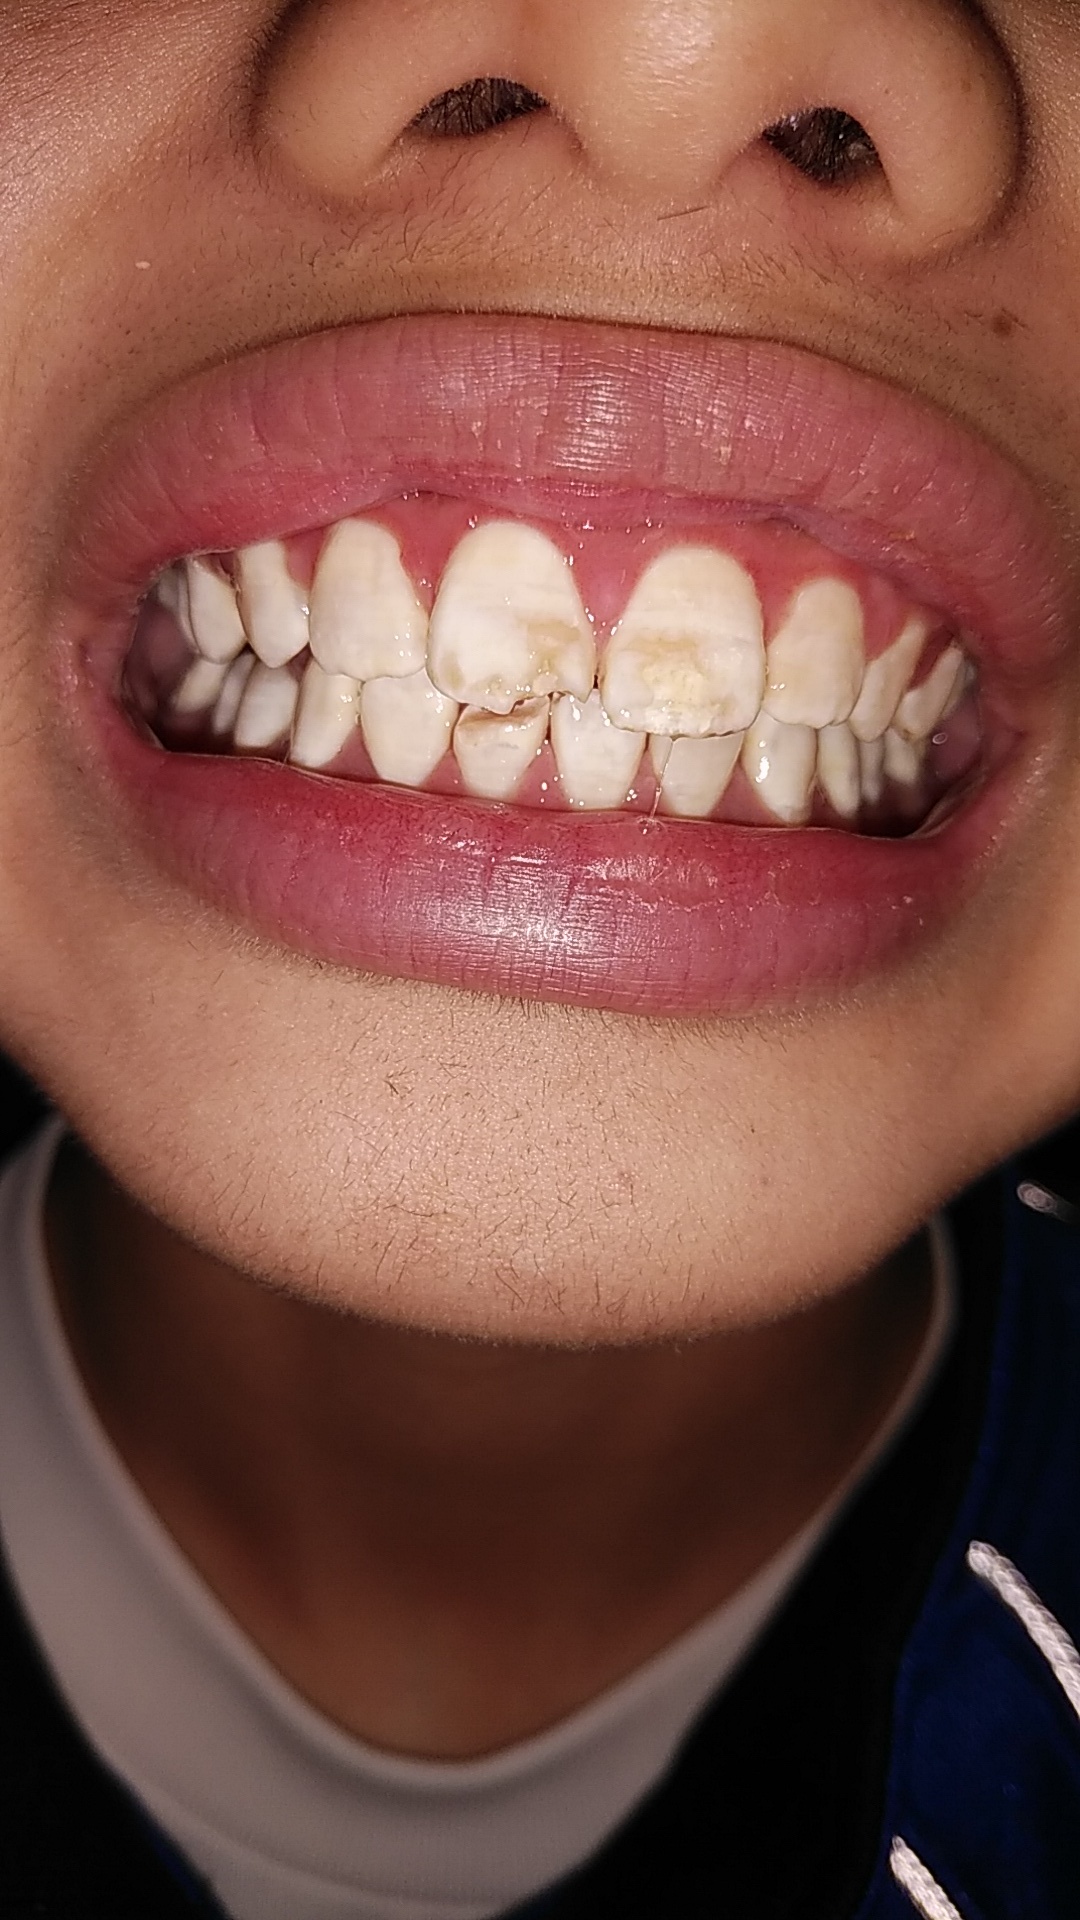

インビザラインやマウスガード矯正による酸蝕に注意

最近10代のインビザラインによる歯並び矯正が多くなっております。 しかし、インビザラインの公...

新型コロナ禍のストレスにより摂食障害による歯の相談が急増

新型コロナ禍における自粛のために、人と話す機会が減り、摂食障害の悪化や再発が多くなっていると言...